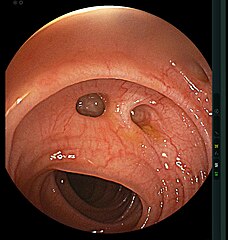

Π Π΅ΠΊΡΠΎΡΠΎΠΌΠ°Π½ΠΎΡΠΊΠΎΠΏΠΈΡ ΠΈ ΠΊΠΎΠ»ΠΎΠ½ΠΎΡΠΊΠΎΠΏΠΈΡ — ΡΠ½Π΄ΠΎΡΠΊΠΎΠΏΠΈΡΠ΅ΡΠΊΠΈΠ΅ ΠΌΠ΅ΡΠΎΠ΄Ρ ΠΎΠ±ΡΠ»Π΅Π΄ΠΎΠ²Π°Π½ΠΈΡ. ΠΡ ΡΡΡΡ Π·Π°ΠΊΠ»ΡΡΠ°Π΅ΡΡΡ Π² Π²Π²Π΅Π΄Π΅Π½ΠΈΠΈ ΠΊΠ°ΠΌΠ΅ΡΡ Π² ΡΠΎΠ»ΡΡΡΠΉ ΠΊΠΈΡΠ΅ΡΠ½ΠΈΠΊ. ΠΠ° ΠΈΠ·ΠΎΠ±ΡΠ°ΠΆΠ΅Π½ΠΈΠΈ, ΠΊΠΎΡΠΎΡΠΎΠ΅ Π²ΡΠ²ΠΎΠ΄ΠΈΡΡΡ Π½Π° ΠΌΠΎΠ½ΠΈΡΠΎΡ, ΠΌΠΎΠΆΠ½ΠΎ ΡΠ²ΠΈΠ΄Π΅ΡΡ ΡΠ°ΠΌ Π΄ΠΈΠ²Π΅ΡΡΠΈΠΊΡΠ», ΠΎΠΏΡΠ΅Π΄Π΅Π»ΠΈΡΡ ΠΈΡΡΠΎΡΠ½ΠΈΠΊ ΠΊΡΠΎΠ²ΠΎΡΠ΅ΡΠ΅Π½ΠΈΡ, ΠΏΡΠΎΠ²Π΅ΡΡΠΈ Π΄ΠΈΡΡΠ΅ΡΠ΅Π½ΡΠΈΠ°Π»ΡΠ½ΡΡ Π΄ΠΈΠ°Π³Π½ΠΎΡΡΠΈΠΊΡ Ρ Π΄ΡΡΠ³ΠΈΠΌΠΈ Π±ΠΎΠ»Π΅Π·Π½ΡΠΌΠΈ.

ΠΠ½Π΄ΠΎΡΠΊΠΎΠΏΠΈΡΠ΅ΡΠΊΠΎΠ΅ ΠΈΡΡΠ»Π΅Π΄ΠΎΠ²Π°Π½ΠΈΠ΅ ΠΈΠ»ΠΈ ΠΊΠΎΠ»ΠΎΠ½ΠΎΡΠΊΠΎΠΏΠΈΡ ΠΏΡΠΈ ΡΡΠΎΠΌ Π½Π΅Π΄ΡΠ³Π΅ ΠΏΡΠ΅Π΄ΡΡΠ°Π²Π»ΡΠ΅Ρ ΡΠΎΠ±ΠΎΠΉ ΠΏΠΎΡΠ΅Π½ΡΠΈΠ°Π»ΡΠ½ΡΡ ΠΎΠΏΠ°ΡΠ½ΠΎΡΡΡ, ΠΏΠΎΡΠΊΠΎΠ»ΡΠΊΡ ΠΈΠΌΠ΅Π΅ΡΡΡ ΡΠΈΡΠΊ ΠΏΠΎΠ²ΡΠ΅ΠΆΠ΄Π΅Π½ΠΈΡ ΠΈ ΡΠ°Π·ΡΡΠ²Π° Π΄ΠΈΠ²Π΅ΡΡΠΈΠΊΡΠ»Π° Ρ ΠΏΠΎΡΠ»Π΅Π΄ΡΡΡΠΈΠΌ ΠΊΡΠΎΠ²ΠΎΡΠ΅ΡΠ΅Π½ΠΈΠ΅ΠΌ ΠΈΠ· Π½Π΅Π³ΠΎ.